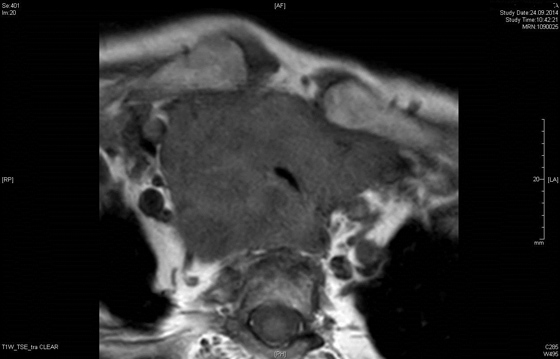

In speziellen Fällen brauchen wir zusätzliche Untersuchungen wie eine Magnetresonanztomographie (MRI) oder eine Computer-Tomographie (CT), um eine die Ausdehnung eines Befundes zu beurteilen.